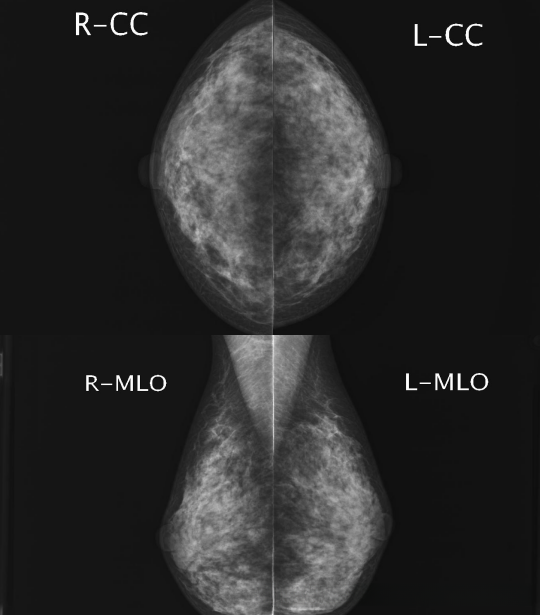

1、影像:轴位片(头足位 CC) 斜位片(MLO)*左右=4张影像

同侧 例如:rcc 或者R-mlo用于定位

左右两侧 例如:R-CC L-CC 用于比较是否不对称,两侧同拍照模式进行对比